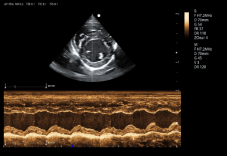

8P2MA ● 3.5-15.0MHz ● Single crystal phased array probe ● For Cardiology of felines |

3P2PA ● 1.0-6.5MHz ● Phased array probe ● For Cardiology of big-sized canines |

5P1PAA ● 2.5-13.0MHz ● Phased array probe ● For Cardiology of small and medium-sized canines |